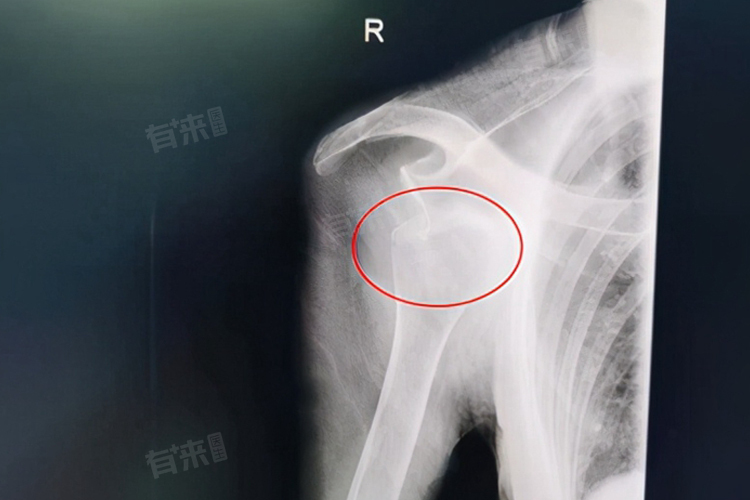

3岁小孩反复脱臼5次,可能是因牵拉肘等外力因素、关节发育不完善、韧带松弛等因素导致。需及时前往骨科或小儿骨科就诊,根据病因采取复位、固定或手术等治疗措施。

- 关节发育不完善:3岁儿童的关节结构还未发育成熟,关节窝较浅,关节囊和韧带也相对薄弱。这使得关节的稳定性较差,在受到轻微外力时,就比成年人更容易发生脱臼。随着年龄增长,关节会逐渐发育完善,但在此之前,孩子仍处于脱臼高发阶段。

- 习惯性脱臼:如果小孩首次脱臼后,没有得到正确的复位和足够时间的固定,受损的关节囊和韧带没有充分修复,关节的稳定性就会下降,从而形成习惯性脱臼。每次脱臼后,关节周围组织的损伤会进一步加重,使得再次脱臼的风险不断增加。